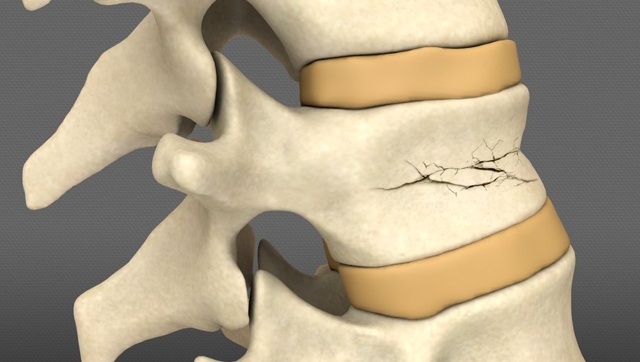

- компрессионные переломы позвонков при остеопорозе;

Компрессионные переломы позвонков тоже могут спровоцировать развитие горба - опухоли и метастазы в позвоночном столбе;

- 4. Остеопороз — заболевание, связанное с недостатком кальция в костной ткани человеческого тела. При поражении шейного отдела позвоночника возникают костные деформации, способствующие образованию горба.